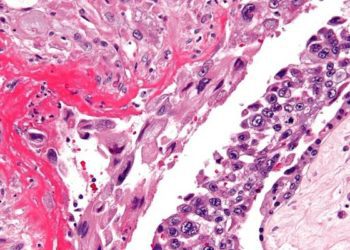

Camrelizumab with apatinib is a well-tolerated treatment for chemo-refractory or relapsed gestational trophoblastic neoplasia

1. Camrelizumab and apatinib treatment provided a 55% objective response rate 2. A complete response was observed in 50% of ...